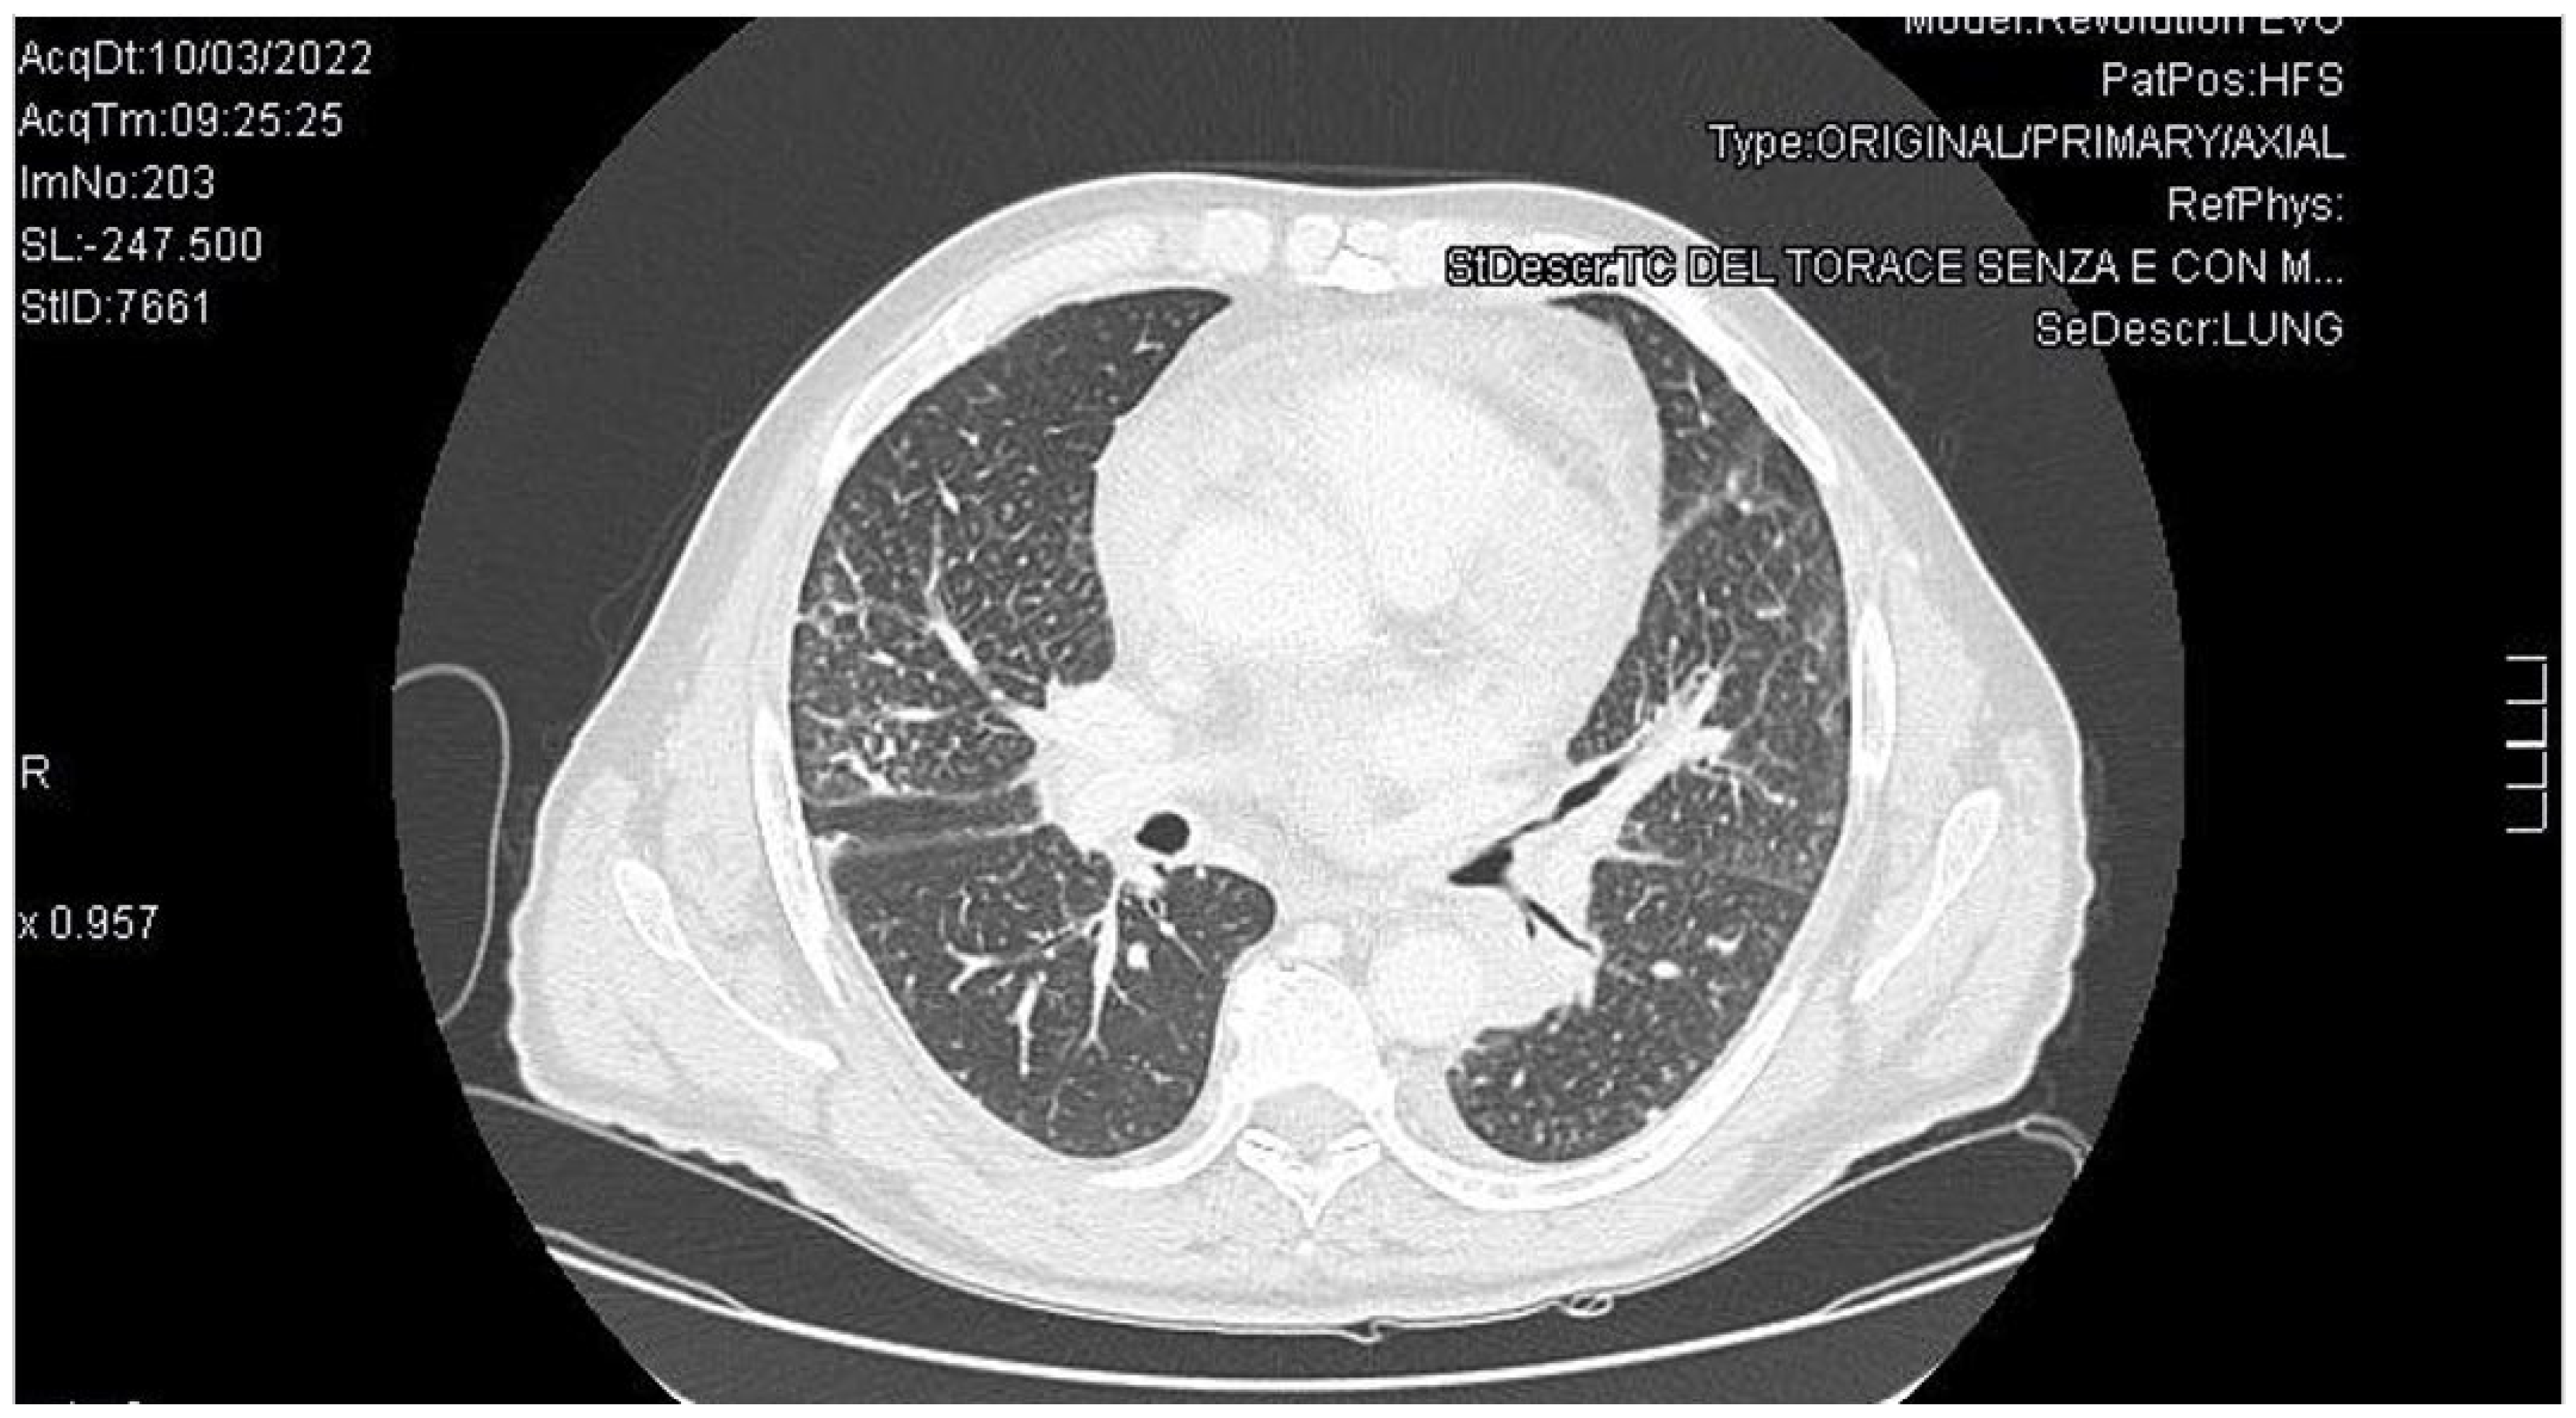

3. Case Report